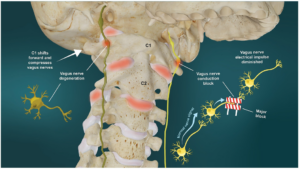

頭痛とめまいを引き起こした頭蓋頸椎の変位

6ヶ月前、約13kgの犬と散歩をしていて、突然頭痛とめまいが発生したとのことでした。

「この日はリードを腰に結んで出かけたのですが、無防備な状態で犬が急に引っ張ったため、体に衝撃がありました」